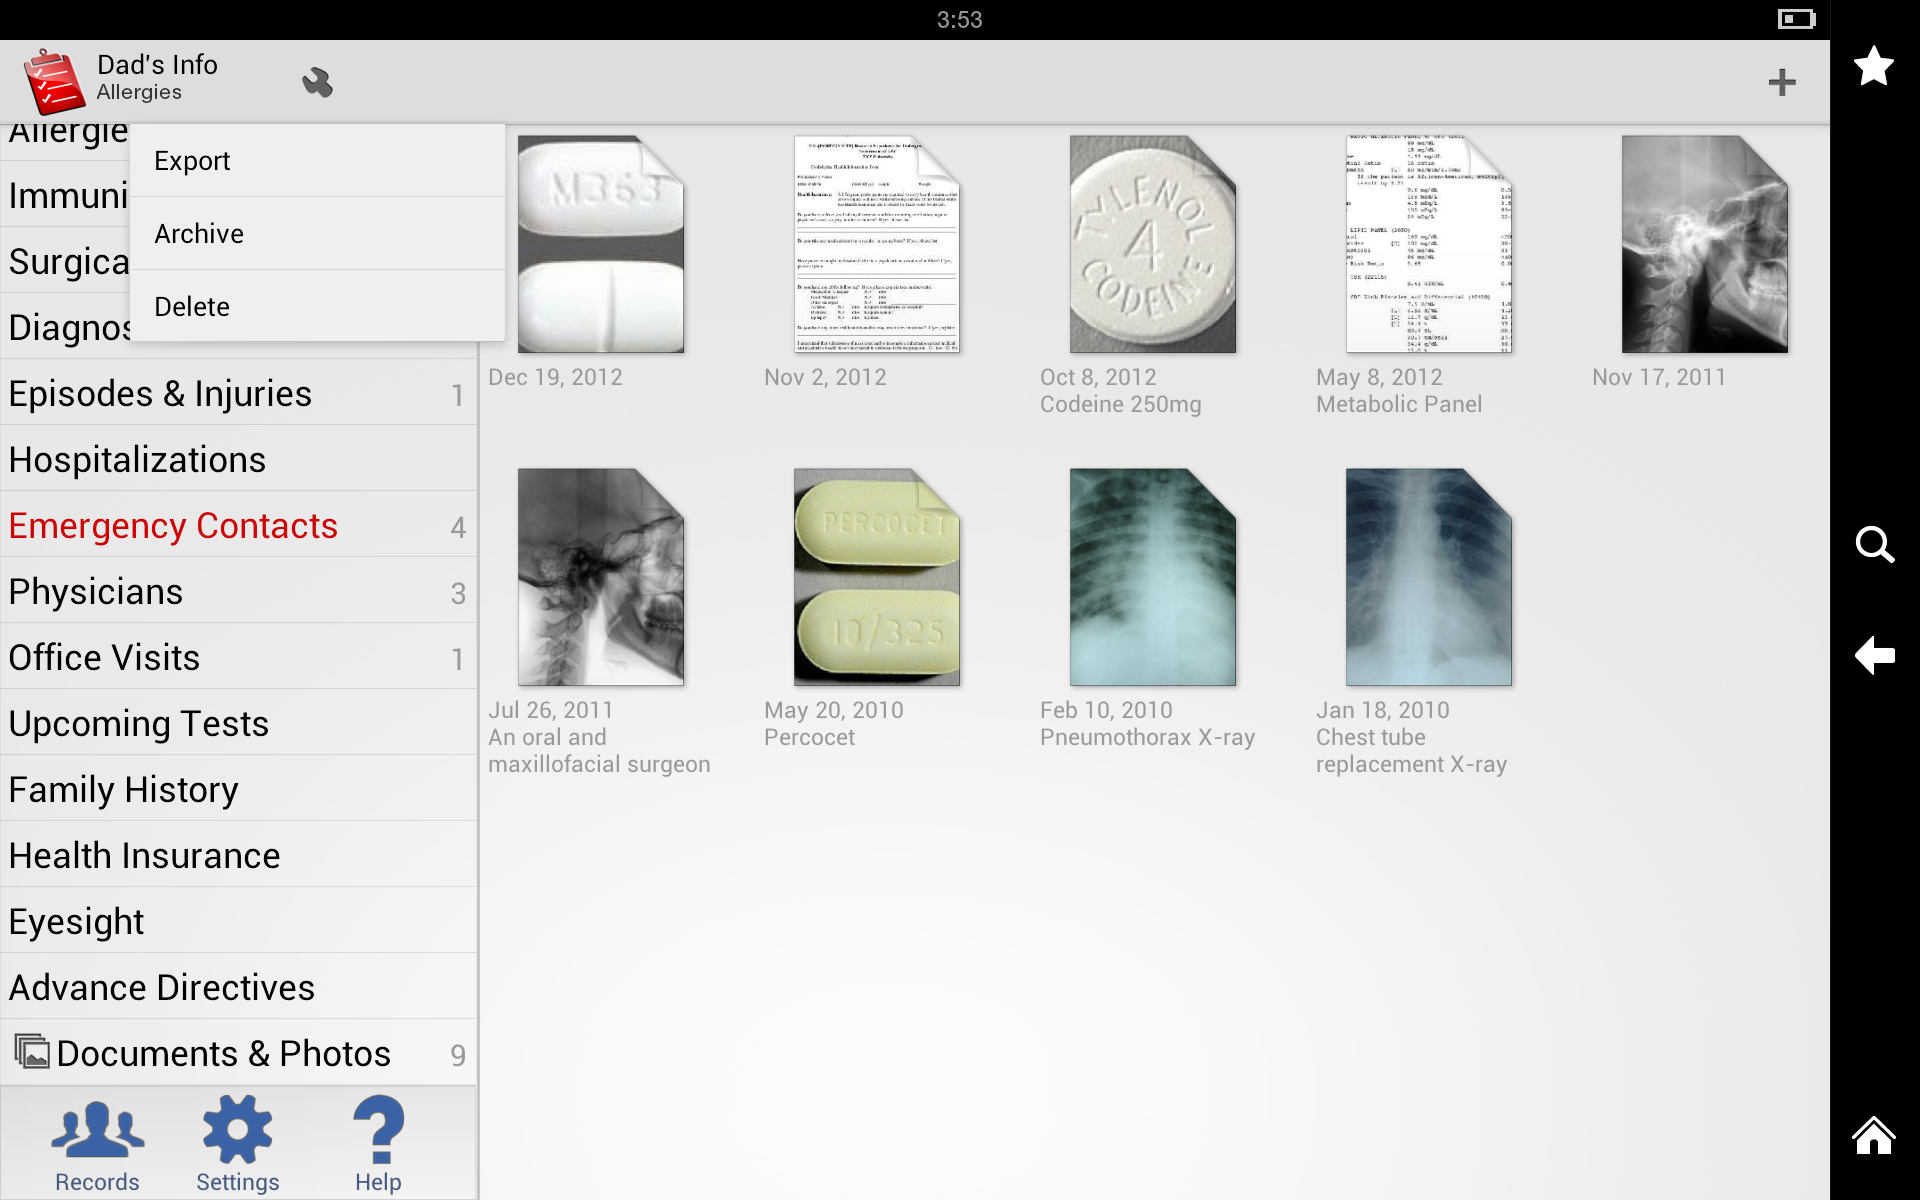

Medication List

With My Medical, you can create a comprehensive list of all the medications you take, including dosage, frequency, and any special instructions. You can set reminders to take your medications and track when you’ve taken them.

With My Medical, you can create a comprehensive list of all the medications you take, including dosage, frequency, and any special instructions. You can set reminders to take your medications and track when you’ve taken them.

Test Results

My Medical allows you to store and track the results of medical tests such as blood work, x-rays, and MRIs. You can also add notes to provide context for the results.

My Medical allows you to store and track the results of medical tests such as blood work, x-rays, and MRIs. You can also add notes to provide context for the results.

User Interface

My Medical has a clean, intuitive interface that makes it easy to navigate and use. The app is organized into tabs for each section, making it easy to find the information you’re looking for. The buttons and menus are clearly labeled, and the app uses intuitive icons to represent different functions.